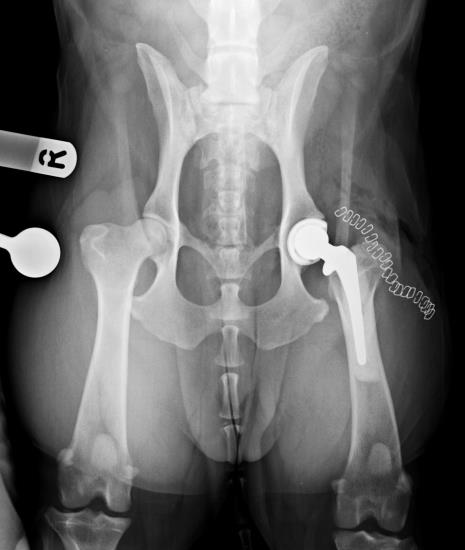

Despite conservative treatment with weight control, hydrotherapy, physiotherapy and multimodal analgesia he was increasingly unable to exercise and reluctant to perform normal day to day tasks. After failing to improve with conservative treatment the decision was made to perform a total hip replacement. A hybrid technique was used with a cementless acetabular component and a cemented femoral stem. He made an excellent recovery following surgery and has now been able to return to hour long walks during which he is happy to run freely. He has also been able to come off all analgesics.

Post-operative ventrodorsal radiograph of the pelvis immediately after total hip replacement using a Biomedtrix BFX cementless acetabular component and CFX cemented femoral stem